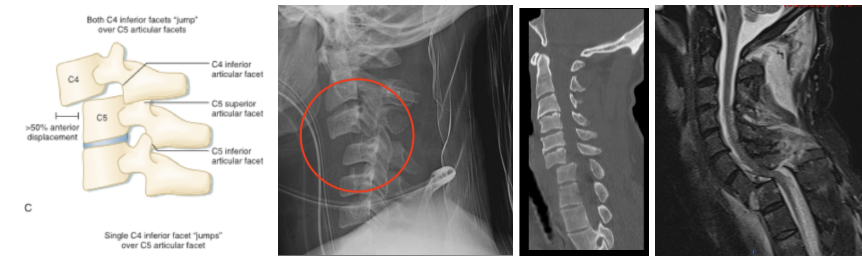

B - Bilateral facet dislocation

1. Caused by extreme neck flexion and anterior subluxation resulting in damage to the annular fibrosis and anterior/posterior longitudinal ligaments

2. Disruption to these complexes result in significant anterior displacement of the superior vertebral body by ≥50% compared to the inferior vertebral body

3. Complications involve injury to the spinal cord and vertebral arteries